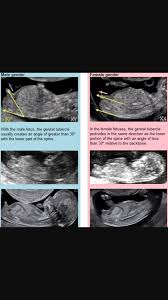

Many mums to be are convinced that the angle that this nub is resting at the angle of the dangle at their 12 week scan can determine the sex of the child. You can have this test as early as your 10th or 12th week of pregnancy. At 12 weeks we may be able to use ultrasound to determine gender based on the angle of the genital tubercle. The 12 week ultrasound is the first chance to get a peek at your baby s sex organs and maybe some idea of what gender your baby is but at 12 weeks it s by no means guaranteed accurate.

The fetus s genitals haven t fully developed at this point so. This is sometimes called nub theory. Your doctor may advise cvs if. One of the most common ways to do this is with an ultrasound most frequently performed at between 18 and 20 weeks of gestation.